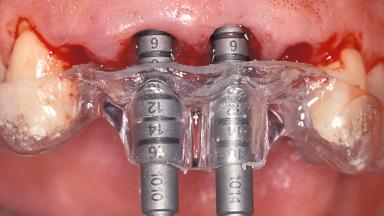

Replacement of the Four Maxillary Incisors with a Fixed Dental Prosthesis Using an Immediate Loading Protocol

In November 2001, a 53-year-old female presented seeking advice and options for treatment of her maxillary incisor teeth. She was dissatisfied with both the functional and esthetic qualities of her existing restorations. Her medical health was excellent, and she reported no contraindications to dental care. On presentation, the patient’s dental health was less than ideal. Although she had no probing depths greater than 3 mm, she suffered from generalized chronic adult periodontitis and displayed multiple sites of bleeding on probing. Her remaining dentition was heavily restored, and many teeth had been endodontically treated. Areas of recurrent dental caries were noted on many teeth. Radiographically and clinically, the maxillary incisor teeth exhibited large areas of active caries, and after the splinted crowns had been removed, the teeth were determined to be non-restorable.

# of Implants 2

Type of Implants One-Piece

Placement Protocol Immediate implant placement

Tooth Site Maxillary incisor or canine